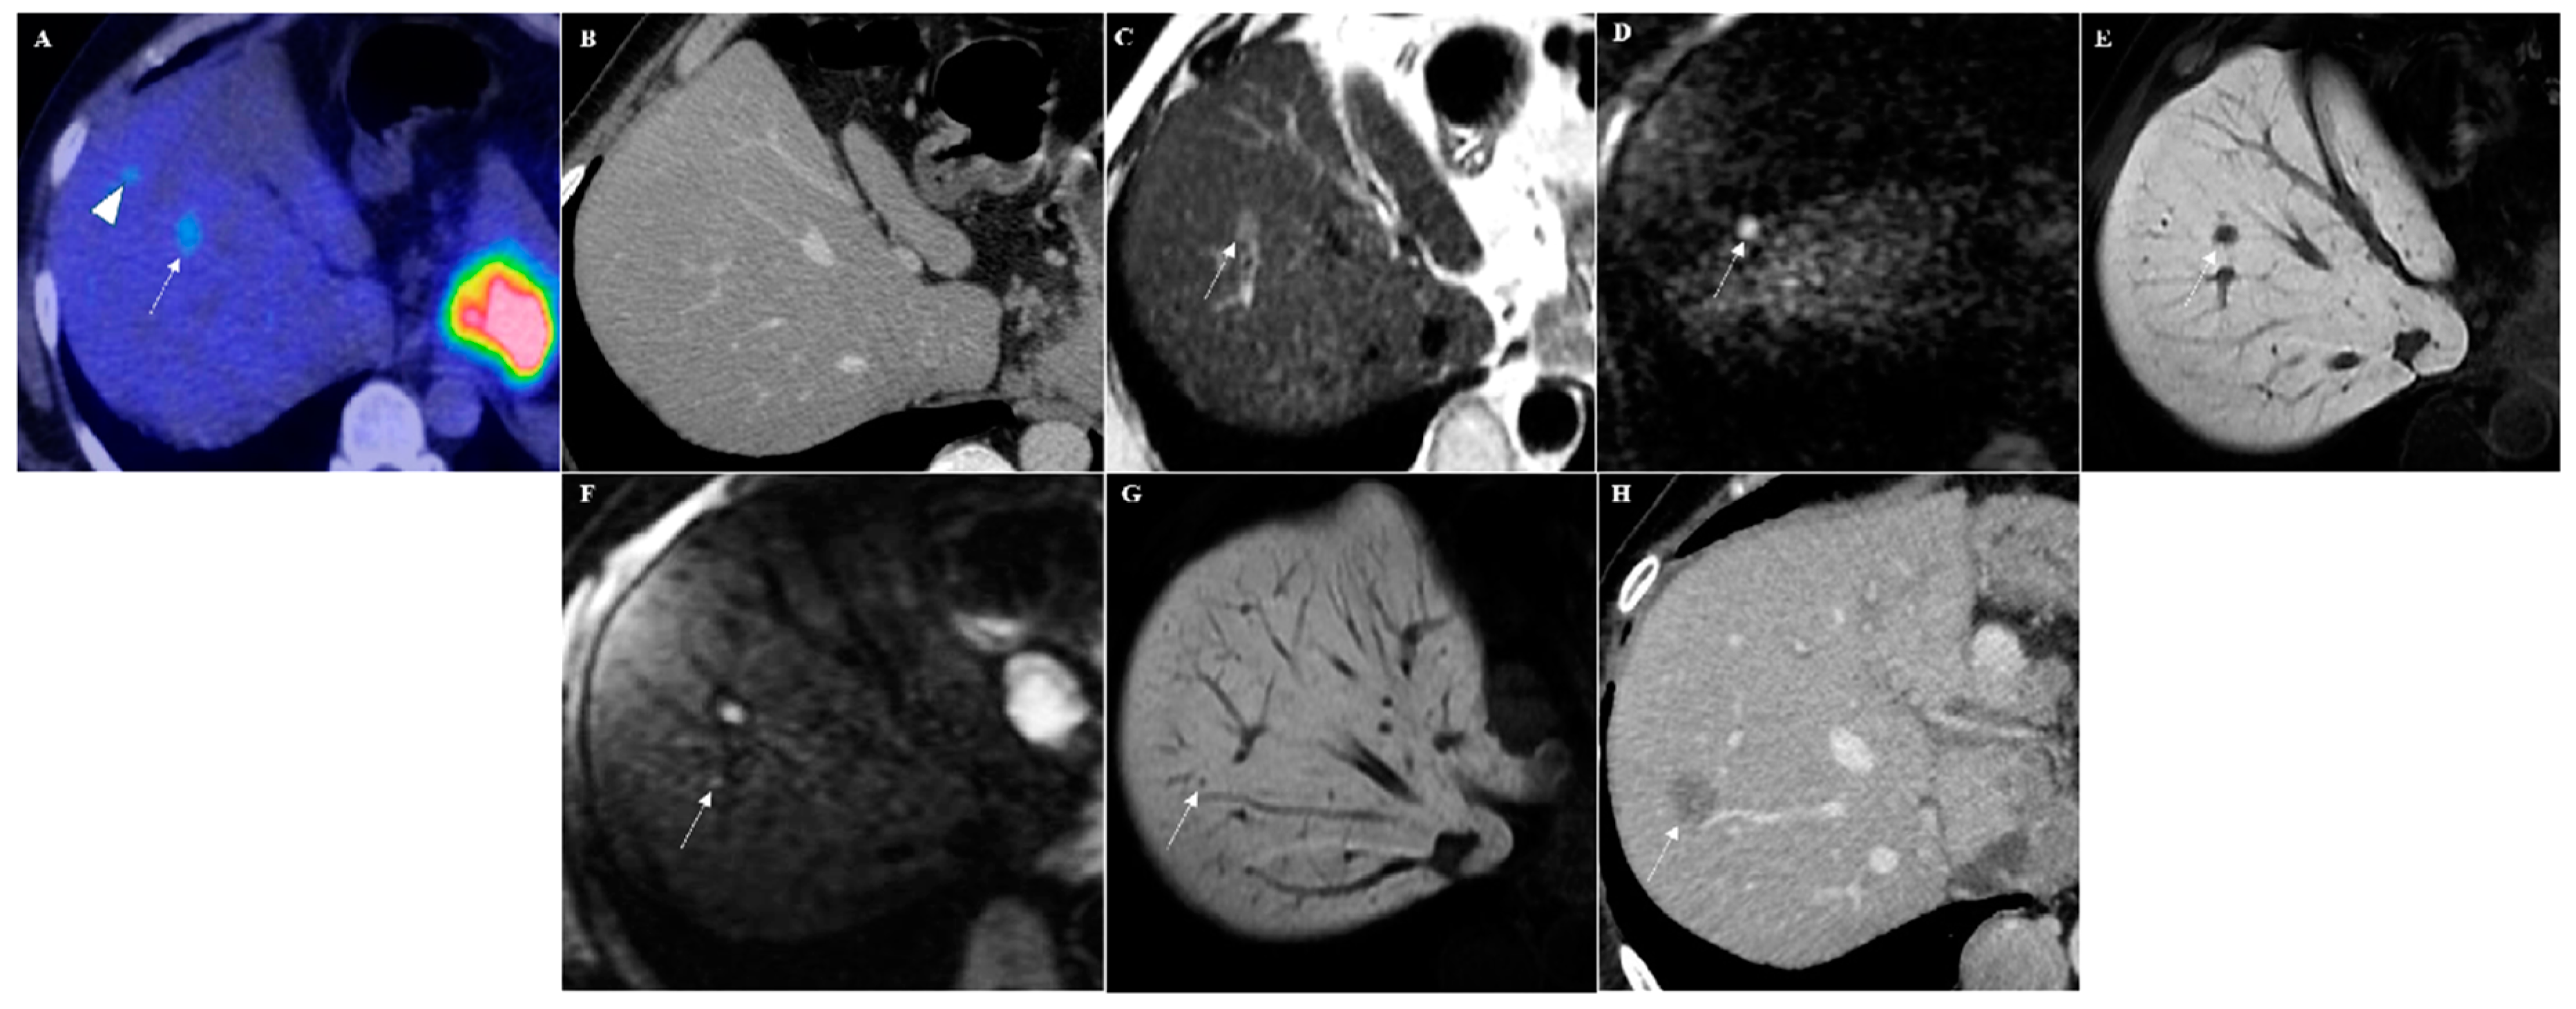

Figure 1.

A 61-year-old male with a clinical history of gastric cancer. (A) 18-fluorideoxyglucose positron emission tomography (18FDG-PET) image shows two focal lesions in the segment VIII of the liver with increased uptake (SUVmax 4.7) (arrowhead and arrow). (B) In the axial computed tomography (CT) scan image, no suspicious lesions were visible. Diffusion-weighted imaging (DWI)-Gd-EOB-DTPA magnetic resonance imaging (MRI) examination showed only one slight hyperintense focal lesion on T2-weighted images (arrow in (C)) with strong hyperintensity in diffusion-weighted image (arrow in (D)) and hypointensity during the hepatobiliary phase (arrow in (E)), suspected for a liver metastasis. Moreover, a very small (2 mm) focal lesion with hyperintensity on diffusion-weighted image (arrow in (F)) and hypointensity during the hepatobiliary phase (arrow in (G)) was also detectable cranially in the same liver segment. An axial contrast-enhanced CT scan performed after six months confirmed this hepatic metastasis (arrow in (H)).